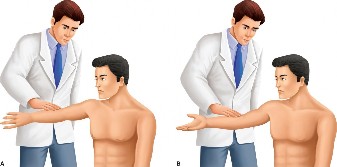

The correct answer is (C). Each RC tendon has specific tests for pathology. The supraspinatus strength test (aka Jobe test) is performed by abducting the shoulder to

90 degrees, bringing the arm in the scapular plane (30 degrees forward), and maximally internally rotating the arm (thumb pointing to the floor) (Fig. 2–1). The test is positive if weakness is found or if pain is experienced. Another test for the supraspinatus is the drop arm test. In the drop arm test, the arm is passively elevated by the examiner to the Jobe position, the patient is asked to attempt to keep it there, and the arm is released by the examiner. The test is positive if the patient is not able to keep the arm elevated and the arm drops.

Figure 2–1 Jobe test.

The belly press test (Answer A) and lift off test (Answer D) are used to evaluate for subscapularis pathology (Figs. 2–3 and 2–4). The hornblower test (Answer B) assesses the teres minor (Fig. 2–2). The external rotation lag test (Answer E) evaluates the infraspinatus.

Figure 2–2_Positive hornblower’s sign. (From Kuzel BR, Grindel S, Papandrea R, Ziegler D. Fatty infiltration and rotator cuff atrophy. _J Am Acad Orthop Surg. 2013;21(10):613–623.)

Figure 2–3_Positive lift-off test with the patient’s left arm in the right picture. Negative lift-off test with the patient’s right arm in the left picture. (From Lyons RP, Green A. Subscapularis tendon tears. _J Am Acad Orthop Surg. 2005;13(5):353–363.)

Figure 2–4_Positive belly-press test with the patient’s left arm in the right picture. Negative belly-press test with the patient’s right arm in the left picture. (From Lyons RP, Green A. Subscapularis tendon tears. _J Am Acad Orthop Surg. 2005;13(5):353–363.)

The O’Brien is one of the most common and is conducted as follows: the shoulder is flexed 90 degrees, internally rotated, and slightly adducted. Resisted shoulder flexion is performed in this position and then repeated with the shoulder externally rotated but still in 90 degrees of flexion and slightly adducted. If pain is experienced with internal rotation that is deep, anterior, and decreased with external rotation, the test is considered positive (see Fig. 2–21A–B).

Figure 2–21(A–B) O’Brien’s active compression test. Left: resisted shoulder flexion in pronation. Right: resisted shoulder flexion in supination. (From Tennent TD, Beach WR, Meyers JF. A review of the special tests associated with shoulder examination. Part II: laxity, instability, and superior labral anterior and posterior (SLAP) lesions. Am J Sports Med. 2003;31(2):301–307.)